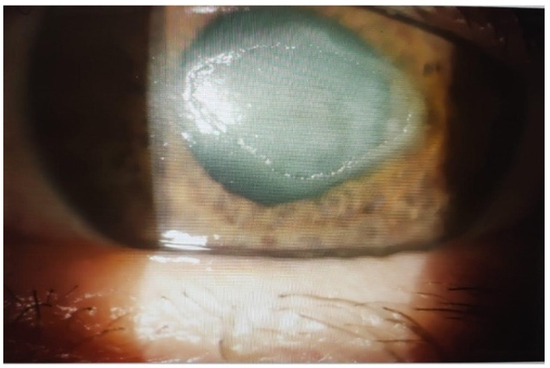

A Rare Case of Alternaria citri Keratitis Successfully Treated with Voriconazole

by Maura Bertazzolo, Giorgia Boaretto, Elena Zani, Massimo Busin, Deborah Cruciani, Silvia Crotti, Chiara Poletti, Roberta Vatri, Alessandra Caracciolo and Cristina Lapucci

The genus Alternaria comprises several species of dematiaceous hyphomycetes known to cause opportunistic infections in humans. Over the past two decades, fungal infections have emerged as a significant cause of morbidity and mortality, particularly among immunocompromised individuals. Such infections often occur following disruption of the skin or corneal epithelial barrier, especially in patients with pre-existing ocular conditions or compromised immune status. This case report describes a rare instance of fungal keratitis (FK) caused by Alternaria citri in a 71-year-old male who presented with an acute onset of eye infection. The patient showed a favorable response to treatment with voriconazole. Full article